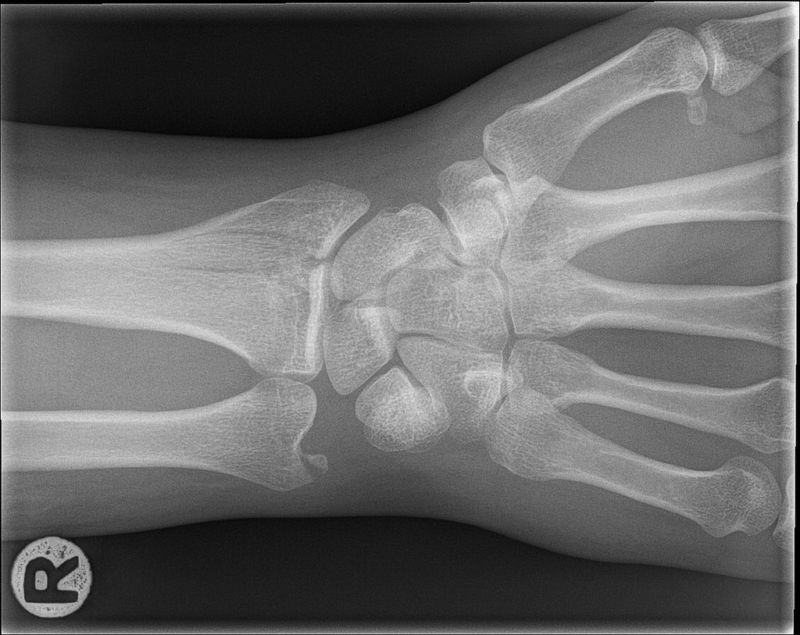

Во второй работе оценивалась способность обнаружения проблем, требующих лечения, в частности, переломы костей. Часто такие проблемы легко увидеть, но небольшой скол или маленькую трещину тяжело заметить даже специалисту. В большинстве случаев диагностика ложится на плечи не специалиста, а доктора, работающего в скорой помощи. Новое исследование не стремится создать ИИ, замещающий докторов, оно лишь хочет им помочь.

Команда попросила 18 хирургов-ортопедов поставить диагноз по 135 000 изображениям потенциальных переломов запястий, а затем использовала эти данные для тренировки алгоритма, свёрточной нейросети с глубинным обучением. Алгоритм использовали для того, чтобы он отмечал области, на которые стоит обратить внимание докторам, не являющимся специалистами по ортопедии. По сути, он помогал им сконцентрироваться на областях, наличие перелома в которых было наиболее вероятно.

В прошлом подобные испытания выдавали слишком большое количество диагнозов, и доктора рекомендовали проведение дополнительных тестов в безобидных случаях. Но в данном случае точность диагноза повысилась, а ложные срабатывания понизились. Чувствительность (или возможность) определять переломы поднялась с 81% до 92%, а точность (способность ставить правильный диагноз) поднялась с 88% до 94%. В сумме это означает, что у докторов скорой помощи количество неправильных диагнозов снизилось бы почти в два раза.